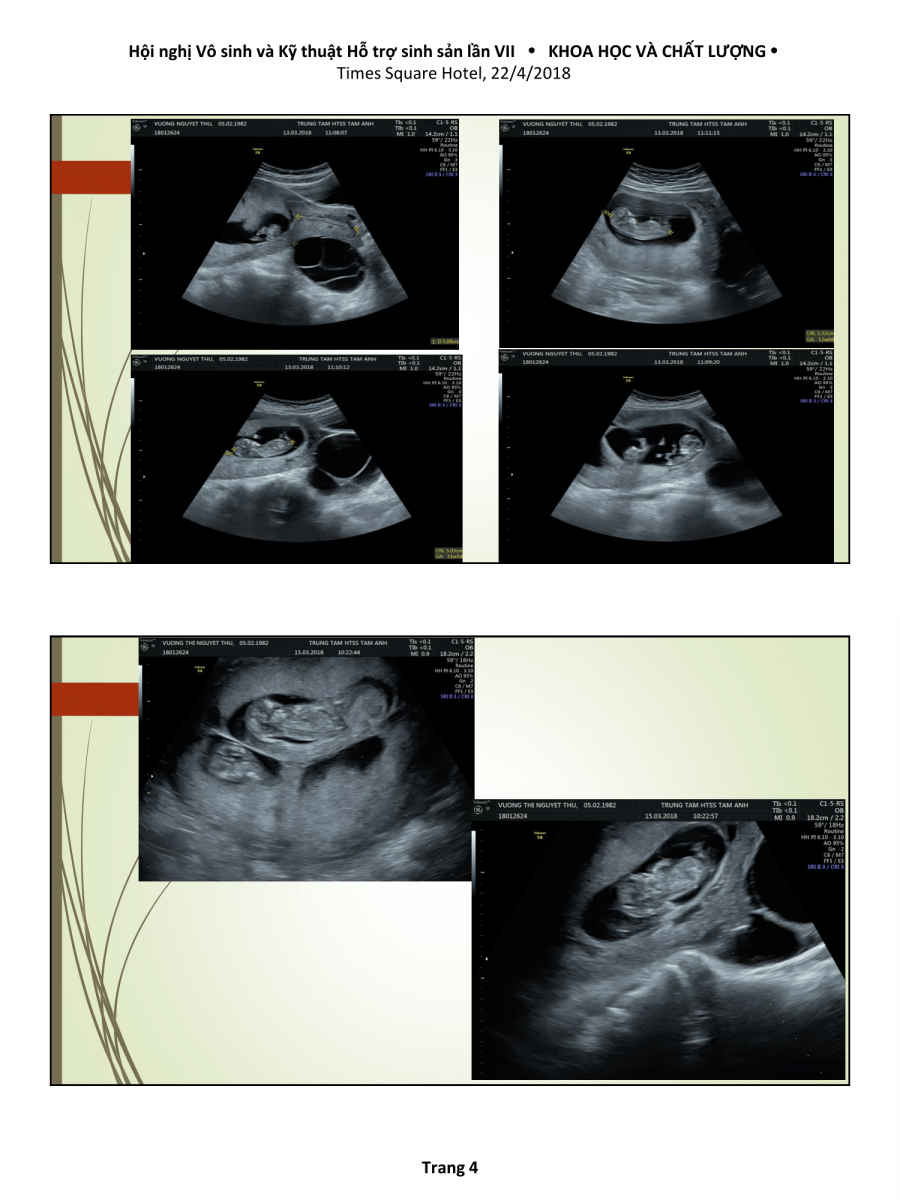

Nhân hai trường hợp giảm thiểu chọn lọc thai to tại bệnh viện Đa khoa Tâm Anh